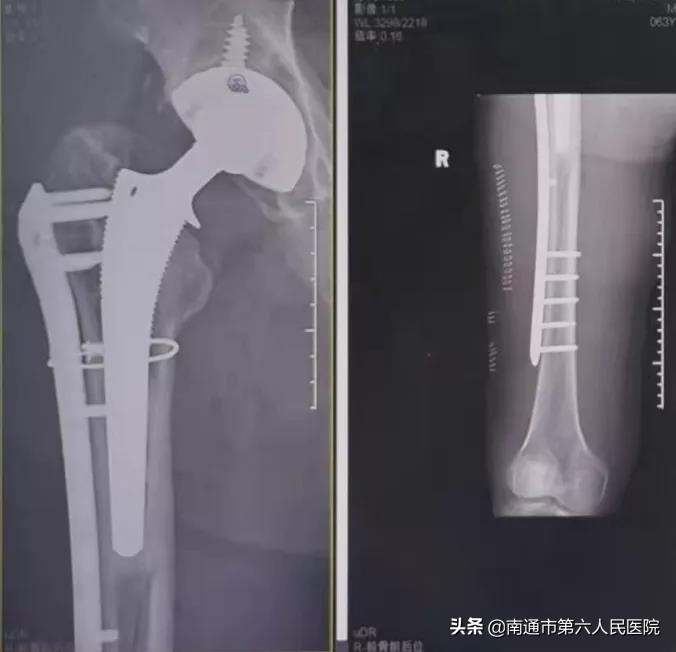

术中,只见孙老伯骨折呈螺旋形,自股骨中段至股骨下段,骨折线近20cm。要在人工髋关节上打钉子、把错位的断端对位并固定,不让其松动脱位,术式复杂,难度系数很大,并非简单的“钉钉子”。

凭借20多年丰富的手术经验,韩元龙副院长仔细将断端进行对位,随后用最长的钢板——13孔股骨锁定加压接骨钢板进行螺钉锁定,并使用线缆环扎固定。手术历时2个小时,骨折对位固定好,稳定性高。术后,孙老伯在骨科加速康复病房的管理下,恢复良好。

与孙老伯同一时间段入院的,还有一位63岁的患者,12年前做了髋关节置换手术,2周前,因外伤致髋关节置换假体远端严重骨折,韩元龙副院长为其成功实施了手术,术后恢复良好,现已康复出院。